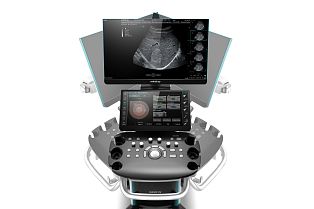

Датчики

Samsung Medison LA2-14A датчик УЗИ линейный

Samsung Medison LA2-9A датчик УЗИ линейный

Samsung Medison L3-12A датчик УЗИ линейный

Samsung Medison LA4-18B датчик УЗИ линейный

Samsung Medison LA3-16A датчик УЗИ линейный

Samsung Medison CA1-7A датчик УЗИ конвексный

Samsung Medison CV1-8A датчик УЗИ объемный конвексный

Samsung Medison CA3-10A датчик УЗИ конвексный

Samsung Medison CA2-9A датчик УЗИ конвексный

Samsung Medison CA2-8A датчик УЗИ конвексный

Samsung Medison EA2-11AR датчик УЗИ внутриполостной

Samsung Medison EА2-11В датчик УЗИ внутриполостной

Samsung Medison EA2-11AV датчик УЗИ внутриполостной

Samsung Medison CF4-9 датчик УЗИ микроконвексный

Samsung Medison EV2-10А датчик УЗИ внутриполостной

Samsung Medison PM1-6A датчик УЗИ секторный

Samsung Medison PA4-12B датчик УЗИ секторный

Samsung Medison PA1-5A датчик УЗИ секторный

Samsung Medison PN2-4 датчик УЗИ секторный

Samsung Medison SP3-8 датчик УЗИ секторный